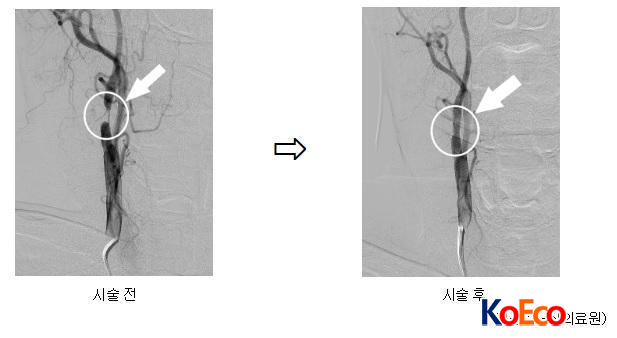

ǷἾͿ Ű(İ߱ ) ԿϿ 28 ڱ(MRA) ˻縦 Ͽ. MRA ˻ 浿 Ǿ, ȭ ɼ Ȳ̾.

̿ ȯ ȣڿ 浿Ƽ/Ʈ ü 6 30 ߾Ӵб , 7 7 浿 Ʈ Ͽ, 18 Ư ȸϿ Ͽ.